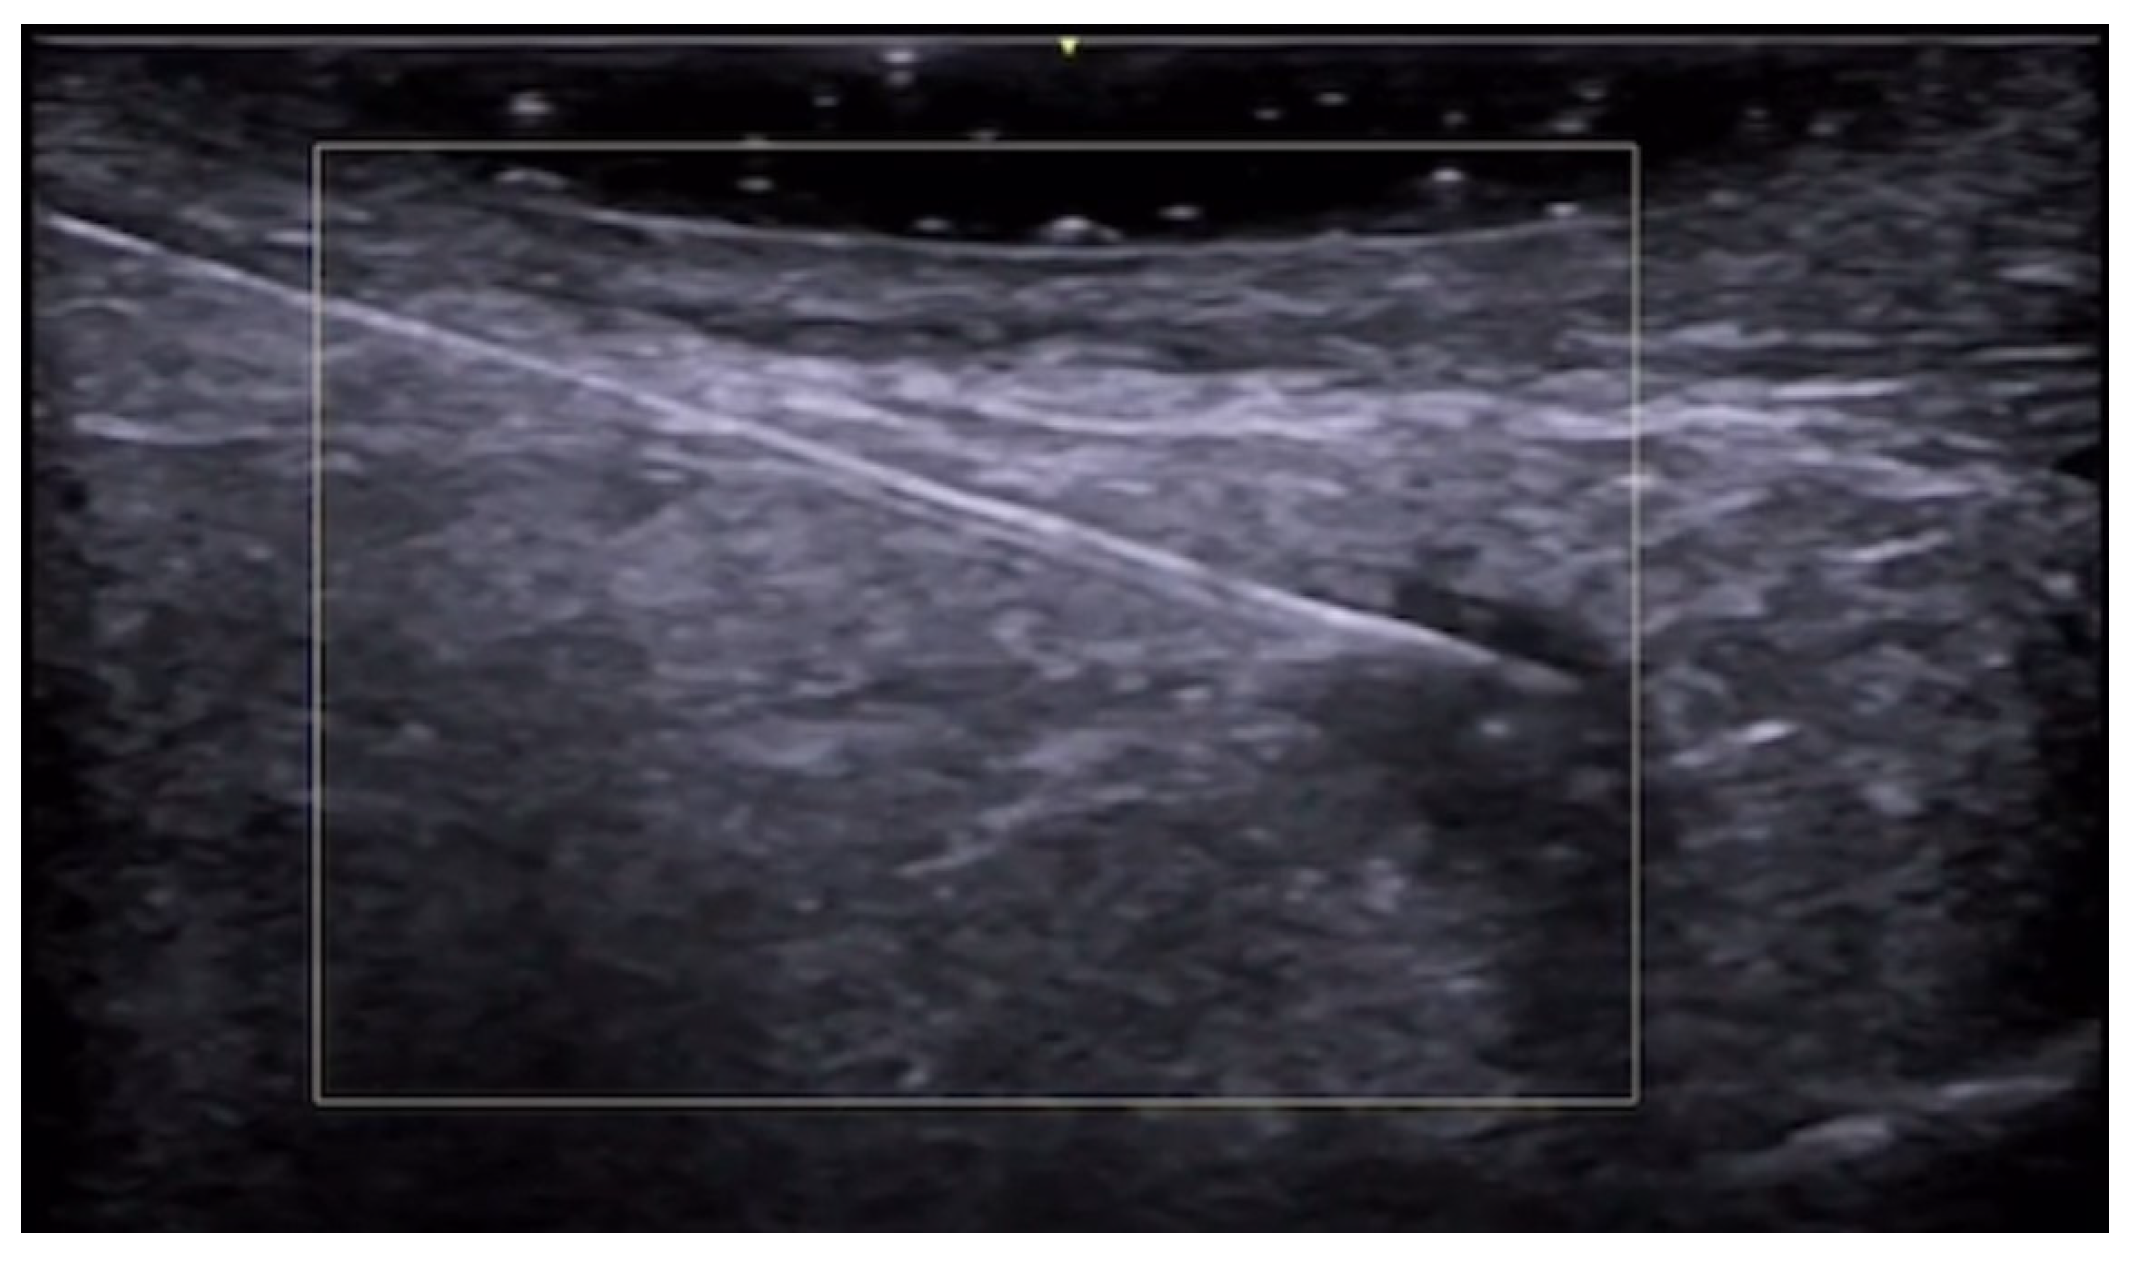

- Del Vecchio, D.; Kenkel, J.M. Practice Advisory on Gluteal Fat Grafting. Aesthetic Surg. J. 2022, 42, 1019–1029. [Google Scholar] [CrossRef]

- Vidal-Laureano, N.; Huerta, C.T.; Perez, E.A.; Earle, S.A. Augmented Safety Profile of Ultrasound-Guided Gluteal Fat Transfer: Retrospective Study with 1815 Patients. Aesthetic Surg. J. 2024, 44, NP263–NP270. [Google Scholar] [CrossRef] [PubMed]

- Elsaftawy, A.; Ostrowski, P.; Bonczar, M.; Stolarski, M.; Gabryszuk, K.; Bonczar, T. Buttock Augmentation with Ultrasonic Liposuction and Ultrasound-Guided Fat Grafting: A Retrospective Analysis Based on 185 Patients. J. Clin. Med. 2024, 13, 1526. [Google Scholar] [CrossRef]

- Elsaftawy, A.; Ostrowski, P.; Bonczar, M.; Stolarski, M.; Gabryszuk, K.; Bonczar, T. Enhancing Buttock Contours: A Safer Approach to Gluteal Augmentation with Ultrasonic Liposuction, Submuscular Implants, and Ultrasound-Guided Fat Grafting. J. Clin. Med. 2024, 13, 2856. [Google Scholar] [CrossRef]

- Wang, B.; He, P.; Zhao, R. B-ultrasound-assisted gluteal fat grafting in Asians: A prospective study of quantitative results from three-dimensional imaging and B-ultrasound analysis. J. Plast. Reconstr. Aesthetic Surg. 2024, 94, 12–19. [Google Scholar] [CrossRef] [PubMed]